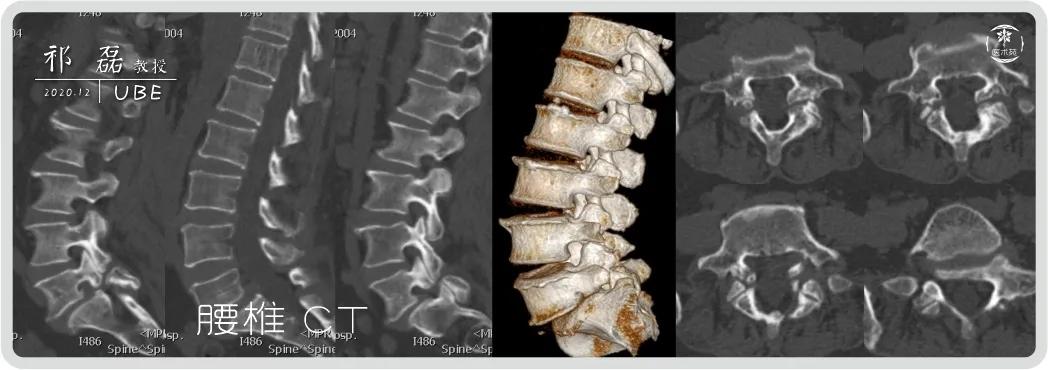

山东大学齐鲁医院祁磊教授行机器人辅助下ube内镜腰椎